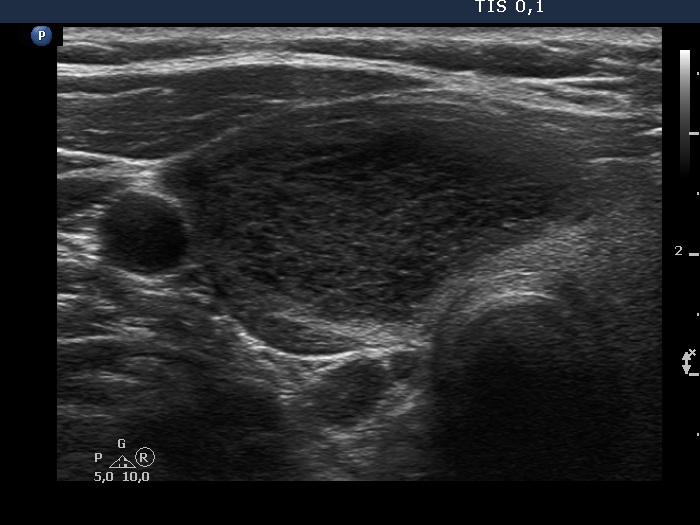

First examination (first, third and fifth rows of images):

Ultrasonography. The thyroid was echonormal and contained multiple inhomogeneous, partly blurred hypoechogenic and moderately hypoechogenic discrete lesions. Multiple lymph nodes were found on both sides of the neck.

Cytology was performed from 3 different thyroid lesions and resulted in a pattern corresponding to non Hodgkin lymphoma.